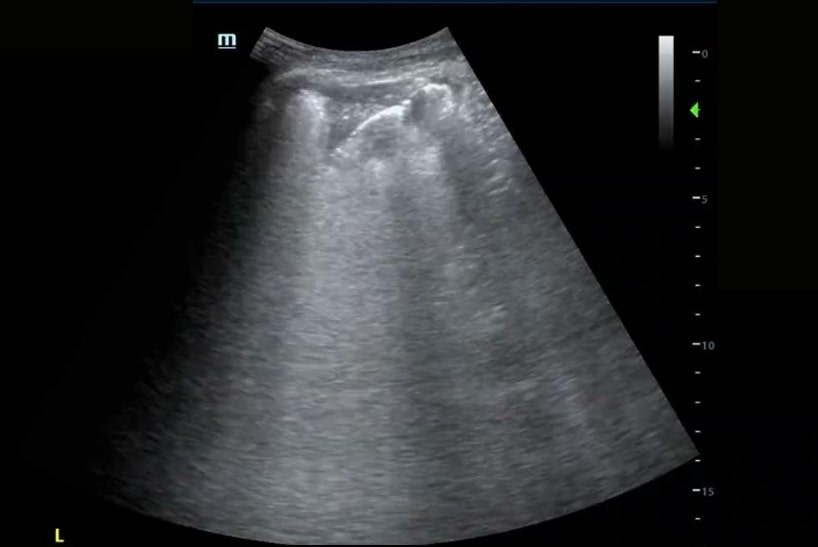

A significant portion of our current knowledge in lung ultrasound stems from Dr. Daniel Lichtenstein’s landmark paper in 1998. The paper discussed the use of artifacts to differentiate between pulmonary edema and COPD. Since that time some of the nomenclature was later redefined by Dr. Lichtenstein and what was then described as “roughly horizontal parallel reverberating lines” is now called A-lines and what was then called comet-tail artifact is now referred to as B-lines (defined as stretching below 16cm of depth). Additionally comet-tails artifact is now referred to as Z-lines and are defined distinct from B-lines and have no clinical significance:

Learning the “ABCs” of the lung can be helpful for interpretation of sonographic findings.

“B” or B-lines can be seen in pneumonia, pulmonary edema, interstitial lung disease, atelectasis, and acute respiratory distress syndrome (ARDS).

“C” or Consolidations are commonly seen in pneumonia and atelectasis and can be distinguished by clinical context and presence of static vs. dynamic air bronchograms (ABs).

Check out the sonographic images.

Bedside ultrasound revealed the expected diffuse B-lines in the bilateral posterior lower lung zones; however, it also found a consolidation in the left lower lung, seen here with the shred sign as well as a small pleural effusion. Therefore the patient was additionally treated for community-acquired pneumonia, which might not have been addressed without the use of point-of-care ultrasound (POCUS)!